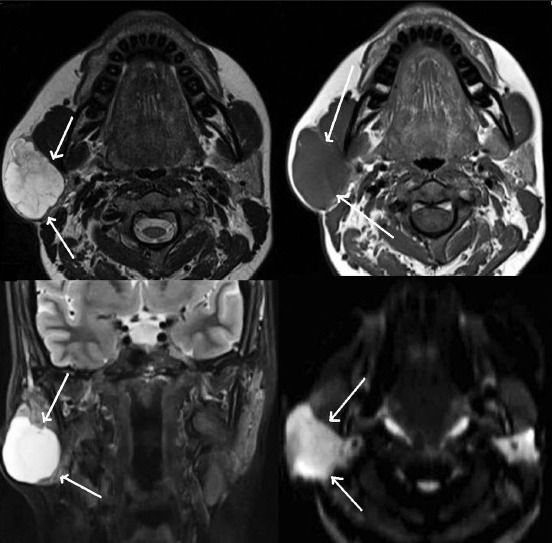

Общие методы обследования больного с подозрением на сиаладеноз включают опрос, осмотр, пальпацию, клинические и биохимические анализы крови и мочи, изучение параметров углеводного обмена (определение глюкозы крови, глюкозо-толерантный тест). Частные диагностические методы направлены на подтверждение невоспалительного и неопухолевого изменения слюнных желез. С помощью УЗИ слюнных желез определяется их увеличение, неоднородность паренхимы, повышение или снижение эхогенности.

Специфические рентгенологические признаки сиаладенозов отсутствуют. При сиалографии может выявляется расширение или сужение слюнных протоков, замедление выведения рентгеноконтрастного препарата из железы. Радиосиалограммы также демонстрируют снижение секреторной способности слюнных желез. Компьютерная томография позволяет обнаружить двухстороннее увеличение объема и плотности железы, исключив опухолевое поражение.

Нередко при сиаладенозе назначается ультразвуковое исследование слюнных желез с целью определения функциональной способности железистой ткани, протоков. Также применяется компьютерная томографии для исключения развития опухолевого процесса, наличия кист, воспалительных инфильтратов.

Сиалография позволяет определить скорость выделения рентгенконтраста из протоков слюнных желез для постановки стадии развития процесса. Нередко для верификации диагноза проводят сиалометрию, цитологическое исследование протокового секрета. Окончательная постановка диагноза проводится путем проведения аспирационной биопсии. Гистологическое исследование выявляет изменение структуру ацинусов, гипертрофию железистой ткани, замещение железы адипозной тканью, отсутствие воспалительной инфильтрации.